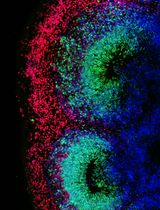

Improved Immunohistochemistry of Mouse Eye Sections Using Davidson's Fixative and Melanin Bleaching

AL Anne Nathalie Longakit

CH Chloe Hess

CZ Christina Zhang

CV Catherine D. Van Raamsdonk

1537 Views

Nov 20, 2025

Immunohistochemistry (IHC) and immunofluorescence (IF) are fundamental molecular biology techniques to assess protein expression. However, the melanin present normally in the eye in the uveal tract (choroid, iris, and ciliary body) and the retinal pigment epithelium (RPE) poses a significant challenge for IHC and IF. This is because melanin interferes with both chromogenic and fluorescent detection methods. Additionally, formalin fixation, which is commonly used for IHC, can result in shrinkage and loss of cellular detail in the eye. This protocol provides an optimized approach using Davidson’s fixative with a hydrogen peroxide bleaching step to eliminate melanin interference in the mouse eye, improving the quality and interpretability of IHC analyses of the uveal tract and RPE. It is particularly useful for the analysis of uveal melanoma.